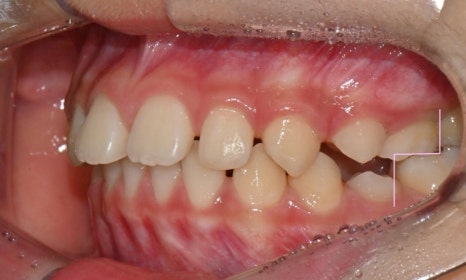

약 9개월간 2급 액티베이터와 헤드기어 착용 후 모습입니다.

2025.5.16.

어금니 관계의 위치변화

치료 결과 하악골은 전방성장하였으며, 과개교합도 많이 개선되었습니다. 헤드기어로 상악골의 성장도 억제되어 돌출되었던 위 앞니 각도도 개선되었고, 위-아래 앞니 사이 간격이 많이 줄었습니다. 위 앞니에 눌려 돌출되었던 하순도 개선되어 straight profile이 완성되었습니다.

환자가 올해 말 출국 계획이 있어서 인비절라인 퍼스트로 최대한 출국 전까지 남아있는 치아 사이 공간을 닫기로 하였습니다. 장치는 총 20단계로 출국 전 마무리를 목표로 장치 착용 중입니다. 영구치가 모두 맹출한 이후 추가적인 교정이 필요할 경우, 방학 때 한국에 들어올 때 워런티 기간 내에 추가교정장치로 마무리해드릴 예정입니다.